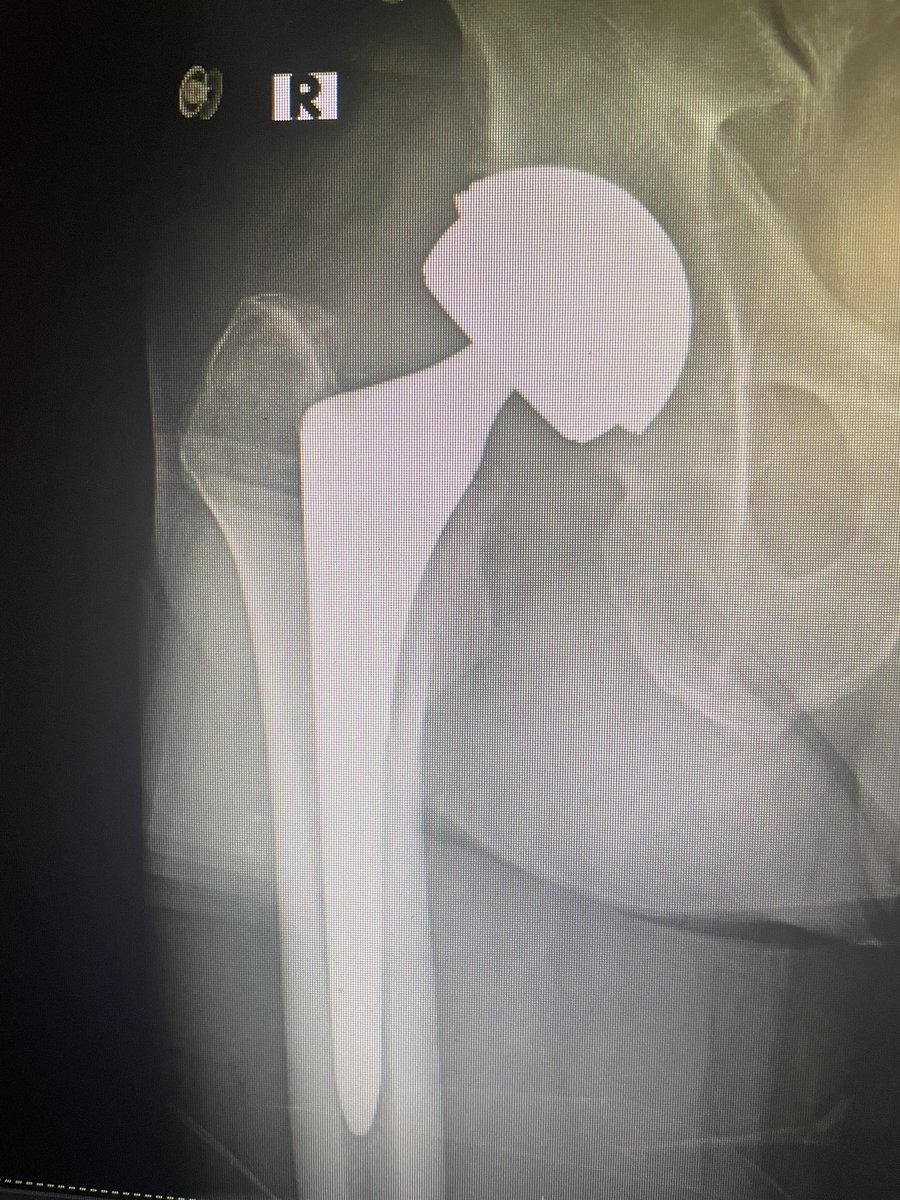

Implant ID? Is this the Zimmer one that has NOT been recalled? Currently asymptomatic